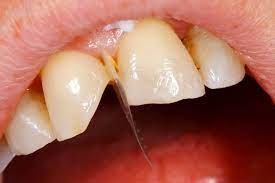

4 Longitudinal Fracture Issues And How They're Treated

Cracked teeth can happen due to a variety of circumstances: trauma due to an accident, chewing on hard food, a weak tooth structure. Sometimes, those cracks result in a type of damage called longitudinal fractures. While these fractures don’t always cause symptoms, they can cause pain and grow bacteria, which can lead to irritation and infection. Luckily, dental professionals can treat longitudinal tooth fractures, and the process to recovery will depend on the type of fracture. Here are the four types to be aware of.

Types of Longitudinal Fractures

1. Craze lines: While craze lines are considered a fracture, they’re not considered a dental emergency and generally do not need treatment. That’s because these lines only affect the tooth enamel and do not cause pain. Teeth grinding, nail-biting, or changing temperatures in the mouth may cause these types of fractures. While these cracks should not cause concern, some adults seek out cosmetic fixes like teeth whitening.

2. Fractured Cusp: Fractured cusps occur when a piece of a tooth’s chewing surface breaks off, typically near a filling. This type of fracture usually does affect your pulp or cause pain and typically can be repaired through a filling or crown.

According to a report in the Journal of Clinical & Diagnostic Research, fractured cusps are the most common type of longitudinal fracture. A number of conditions may cause them:

3. Cracked Tooth: A cracked tooth is when a crack extends from the crown of the tooth toward the root, though the tooth is not split into pieces. This fracture is more extensive than a fractured cusp and, therefore, more likely to affect the nerve of the tooth. There are several possible causes for a cracked tooth, including:

Treatment will vary based on the location and extent of the crack, which your dentist may need to investigate. If the nerve of the tooth is affected, an endodontist might perform a root canal treatment. If the crack extends down below the gumline, the tooth may need to be extracted.

4. Split Tooth: A split tooth is a complete fracture from the crown that extends below the gumline through the middle of the tooth. This is usually the result of an untreated cracked tooth, as the fracture extends over time, it can happen either suddenly or due to the long-term growth of the crack. The tooth may require extraction, but in some cases, an endodontist may save a portion of the tooth and complete a restoration to make the tooth functional.